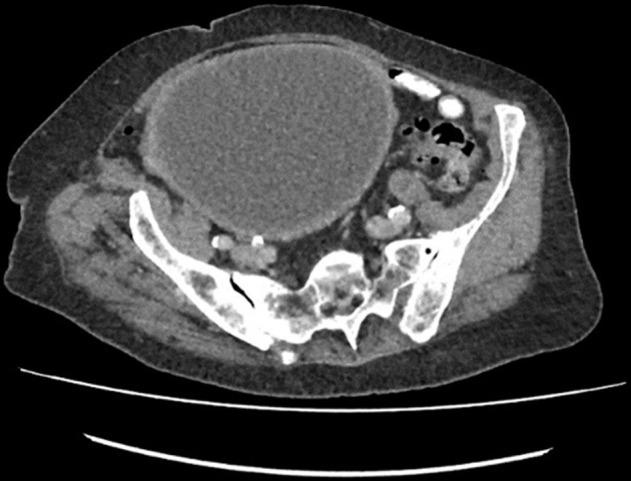

Histiocytic or xanthogranulomatous endometritis (XGE) is an extremely rare benign histopathological entity with only a few cases reported in literature to date. It is characterised by the replacement of endometrial tissue with sheets of foamy histiocytes, giant cells, lymphocytes and plasma cells; calcification and necrosis. It involves chronic inflammation and may be associated with endometrial hyperplasia, endometrial carcinoma and atrophy, causing cervical stenosis and recurrent pyometra, especially in postmenopausal women. We report a case of senile recurrent pyometra masquerading as pyelonephritis clinically and endometrial malignancy radiologically, confirmed later on histology as XGE. Due to deceptive manifestation and rarity of this clinical condition, it is very important for a gynaecologist, radiologist and histopathologist to have a clear understanding of this entity.

组织细胞性或黄色肉芽肿性子宫内膜炎(XGE)是一种极其罕见的良性组织病理学实体,迄今为止文献中仅报道了少数病例。其特征是子宫内膜组织被成片的泡沫状组织细胞、巨细胞、淋巴细胞和浆细胞取代;伴有钙化和坏死。它涉及慢性炎症,可能与子宫内膜增生、子宫内膜癌和萎缩相关,导致宫颈狭窄和复发性脓性子宫积脓,尤其是在绝经后女性中。我们报告一例老年复发性脓性子宫积脓病例,临床上伪装为肾盂肾炎,放射学上疑似子宫内膜恶性肿瘤,后来经组织学确诊为XGE。由于这种临床情况的表现具有欺骗性且罕见,妇科医生、放射科医生和组织病理学家清楚了解这一实体非常重要。